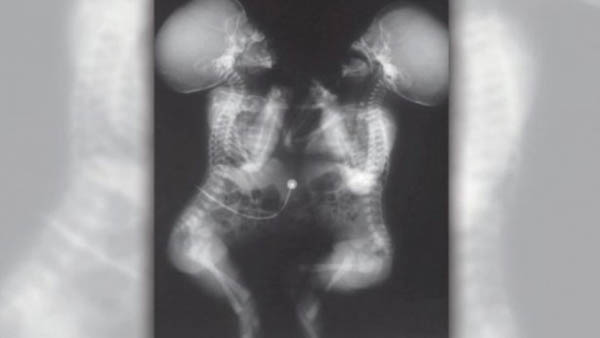

15 மாதக் குழந்தைகளான Nima மற்றும் Dawa Pelden, மார்பிலிருந்து வயிறு வரை ஒட்டியே பிறந்ததோடு இருவருக்கும் சேர்த்து ஒரு கல்லீரல்தான் இருந்தது.

அவுஸ்திரேலிய மருத்துவர்கள் ஆறு மணி நேர அறுவை சிகிச்சைக்குப் பின் வெற்றிகரமாக Nimaவையும் Dawaவையும் பிரித்தெடுத்தனர்.